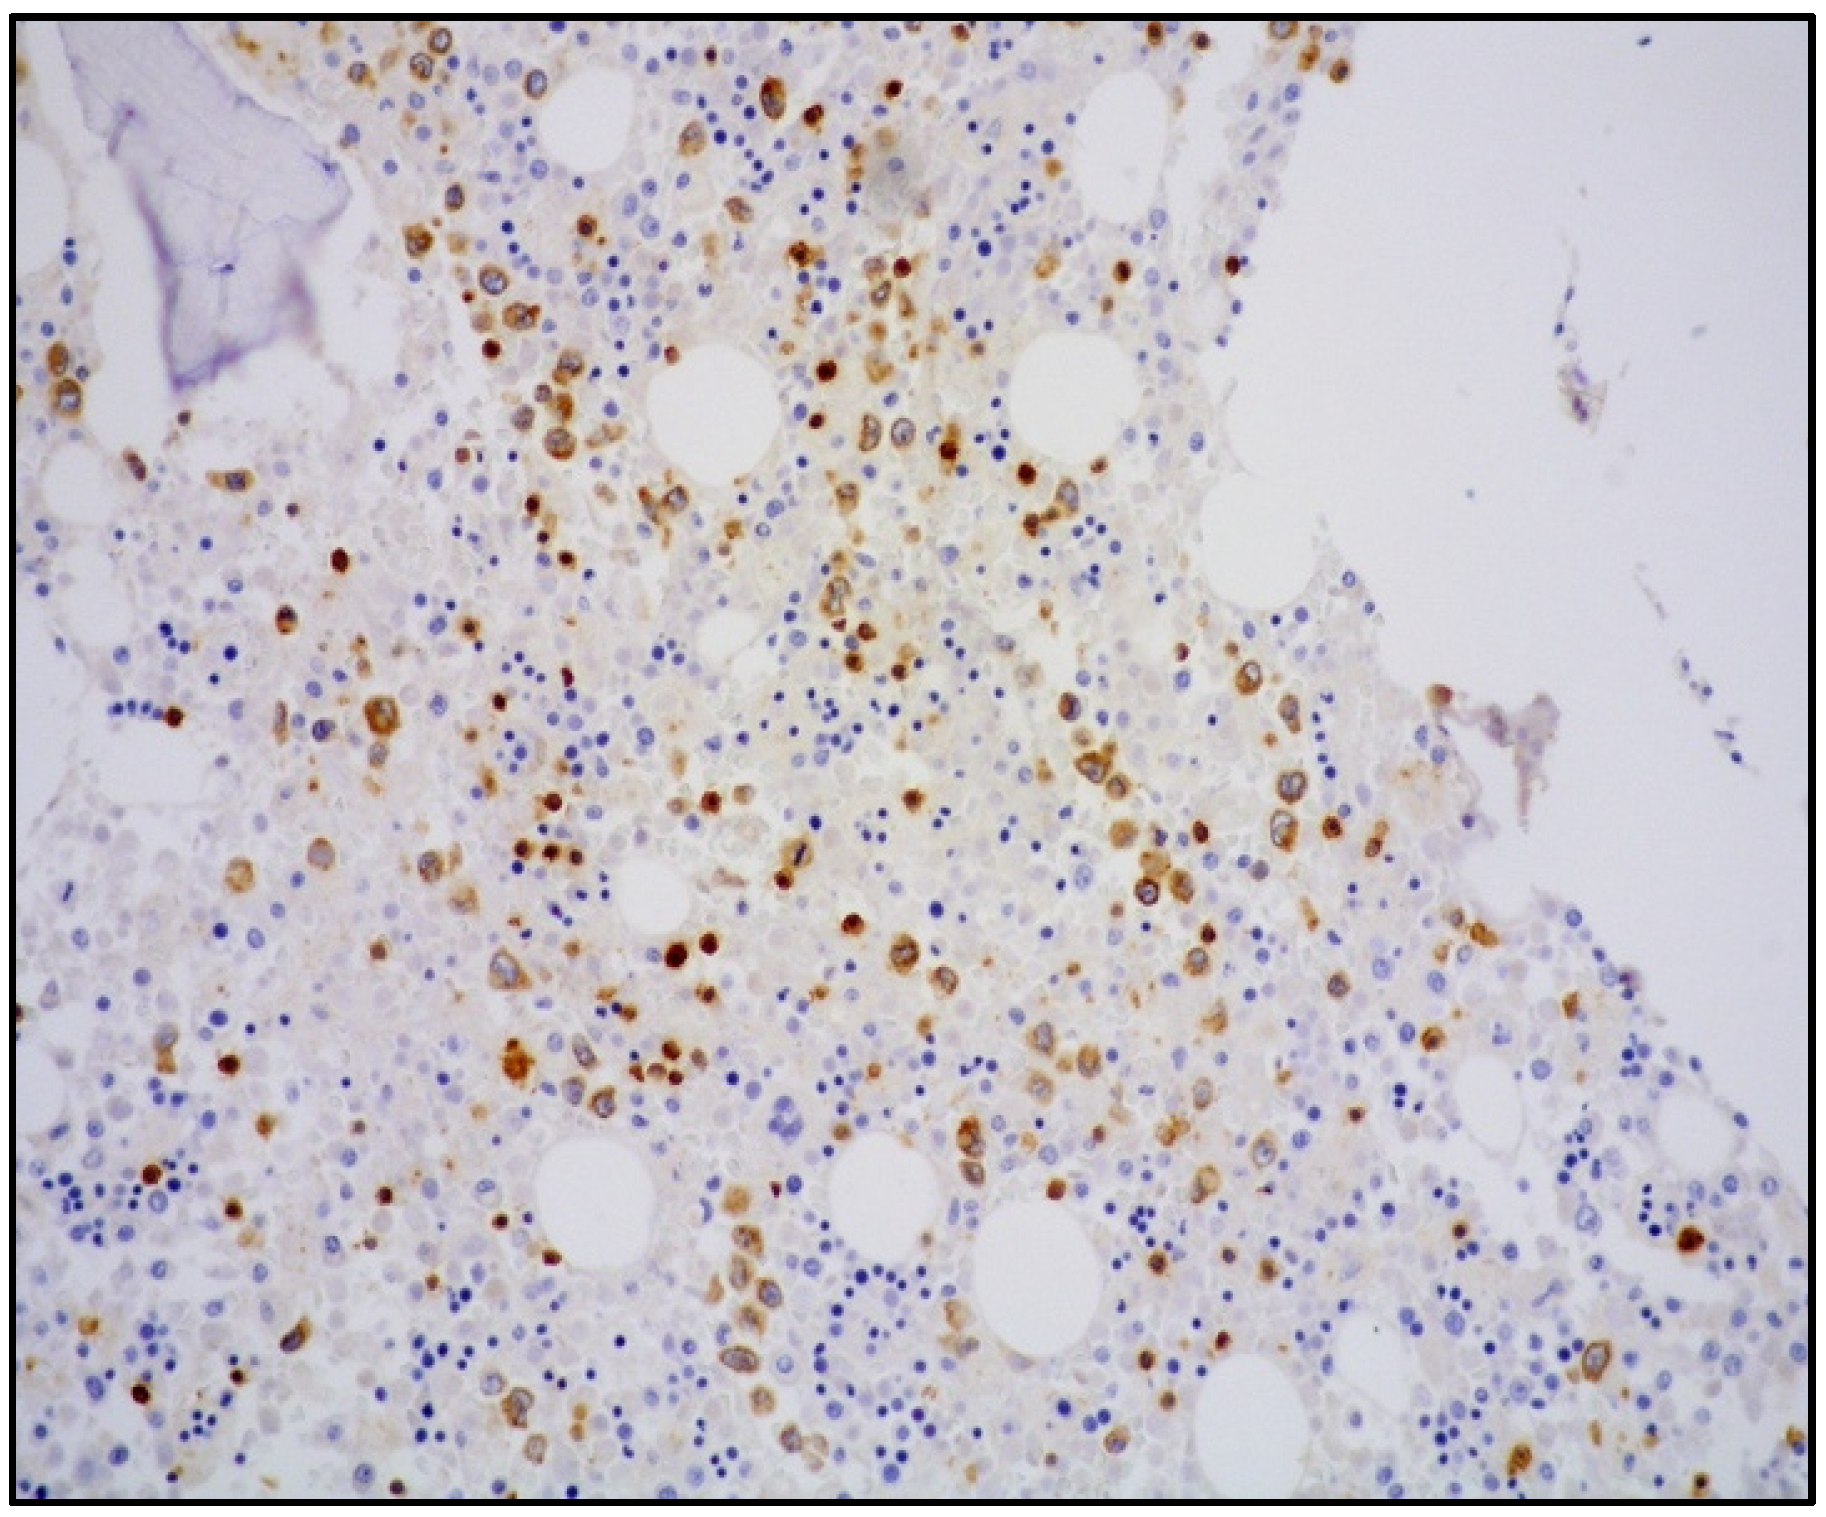

In the majority of cases, there is a strong association with EBV infection and diffuse positive staining with in situ hybridization for EBV-encoded RNA (EBER) (Figure 5).

Figure 5. High-power view showing lung parenchyma with EBER-positive atypical cells within vascular spaces (in situ hybridization for EBV-encoded RNA, 400× magnification, previously unpublished, original image from S.A.).